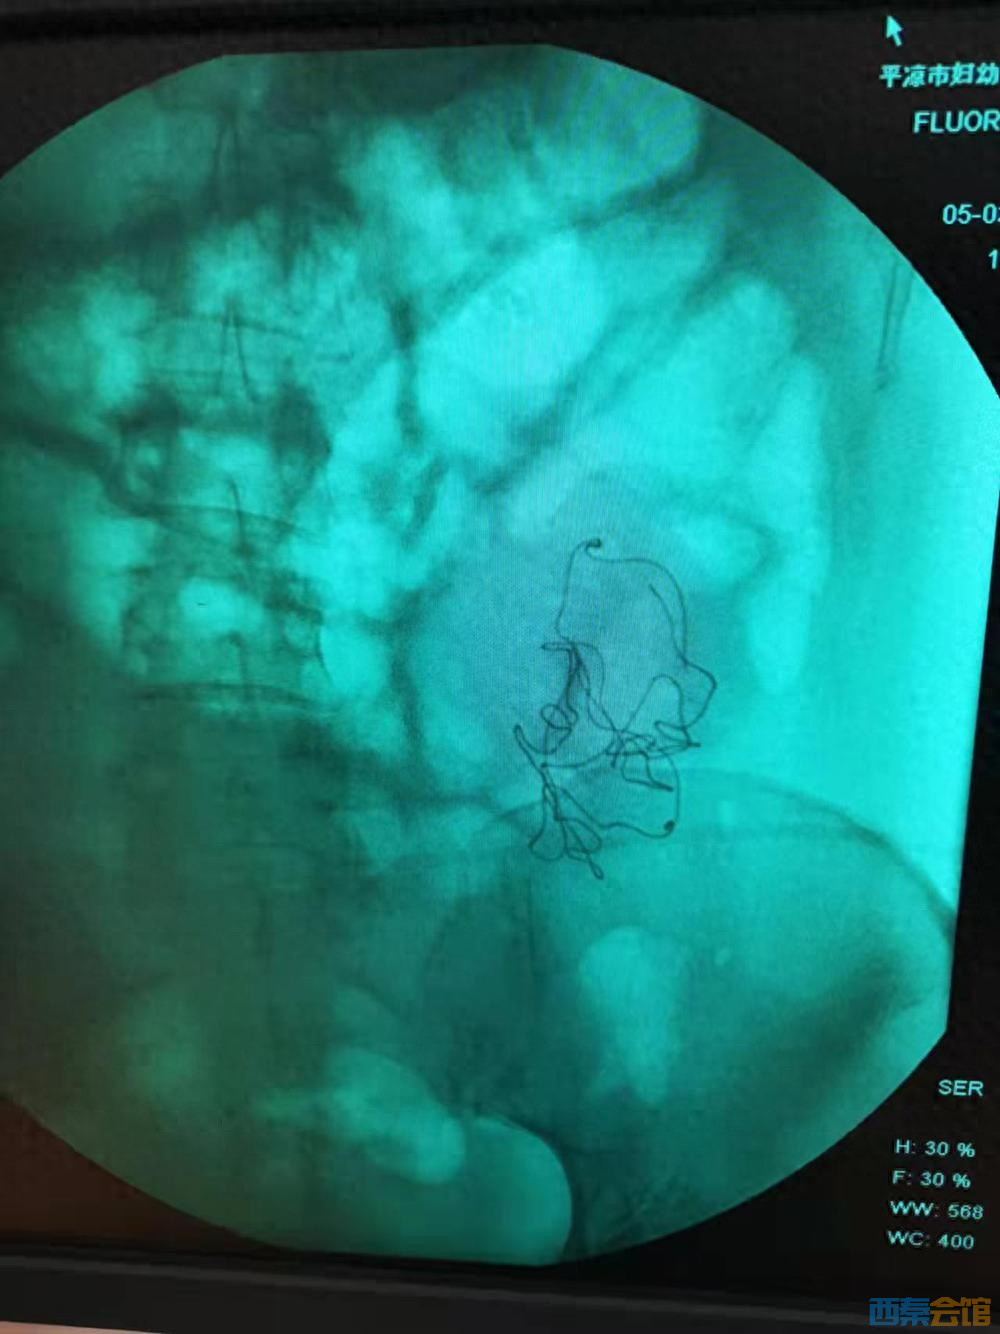

秦红利分娩后,进行X光检查发现异物清晰可见。本文图片均为 受访者供图

而秦红利苏醒后,不仅未见到孩子,还目睹医护人员在产房反复寻找遗失纱布,随后被安排 X 光检查,在无医嘱、无签字的情况下被二次开腹。秦红利称,术中清晰看到医生从腹腔取出带血纱布,X 光影像也显示腹腔内有异物影,可院方手术记录却伪造为 “X 线见少量液平面,腹腔渗血止血”。